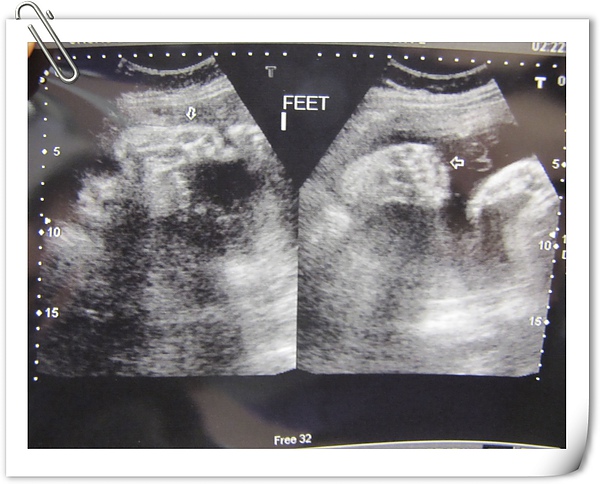

目前寶寶的生長曲線應該是36W4D

超音波頭圍是38W6D(米拔說這像我~~切.....)

手骨、腿骨是39W4D(這應該像米爺爺吧~~~)

MALE是指寶寶的小陰囊,再次證實了Edward是小男生

二隻小腳抬的很高,有正常的五根指頭

終於把手手打開,也是正常的五根,右邊那張只有四根,因為大姆指被含在小嘴裡